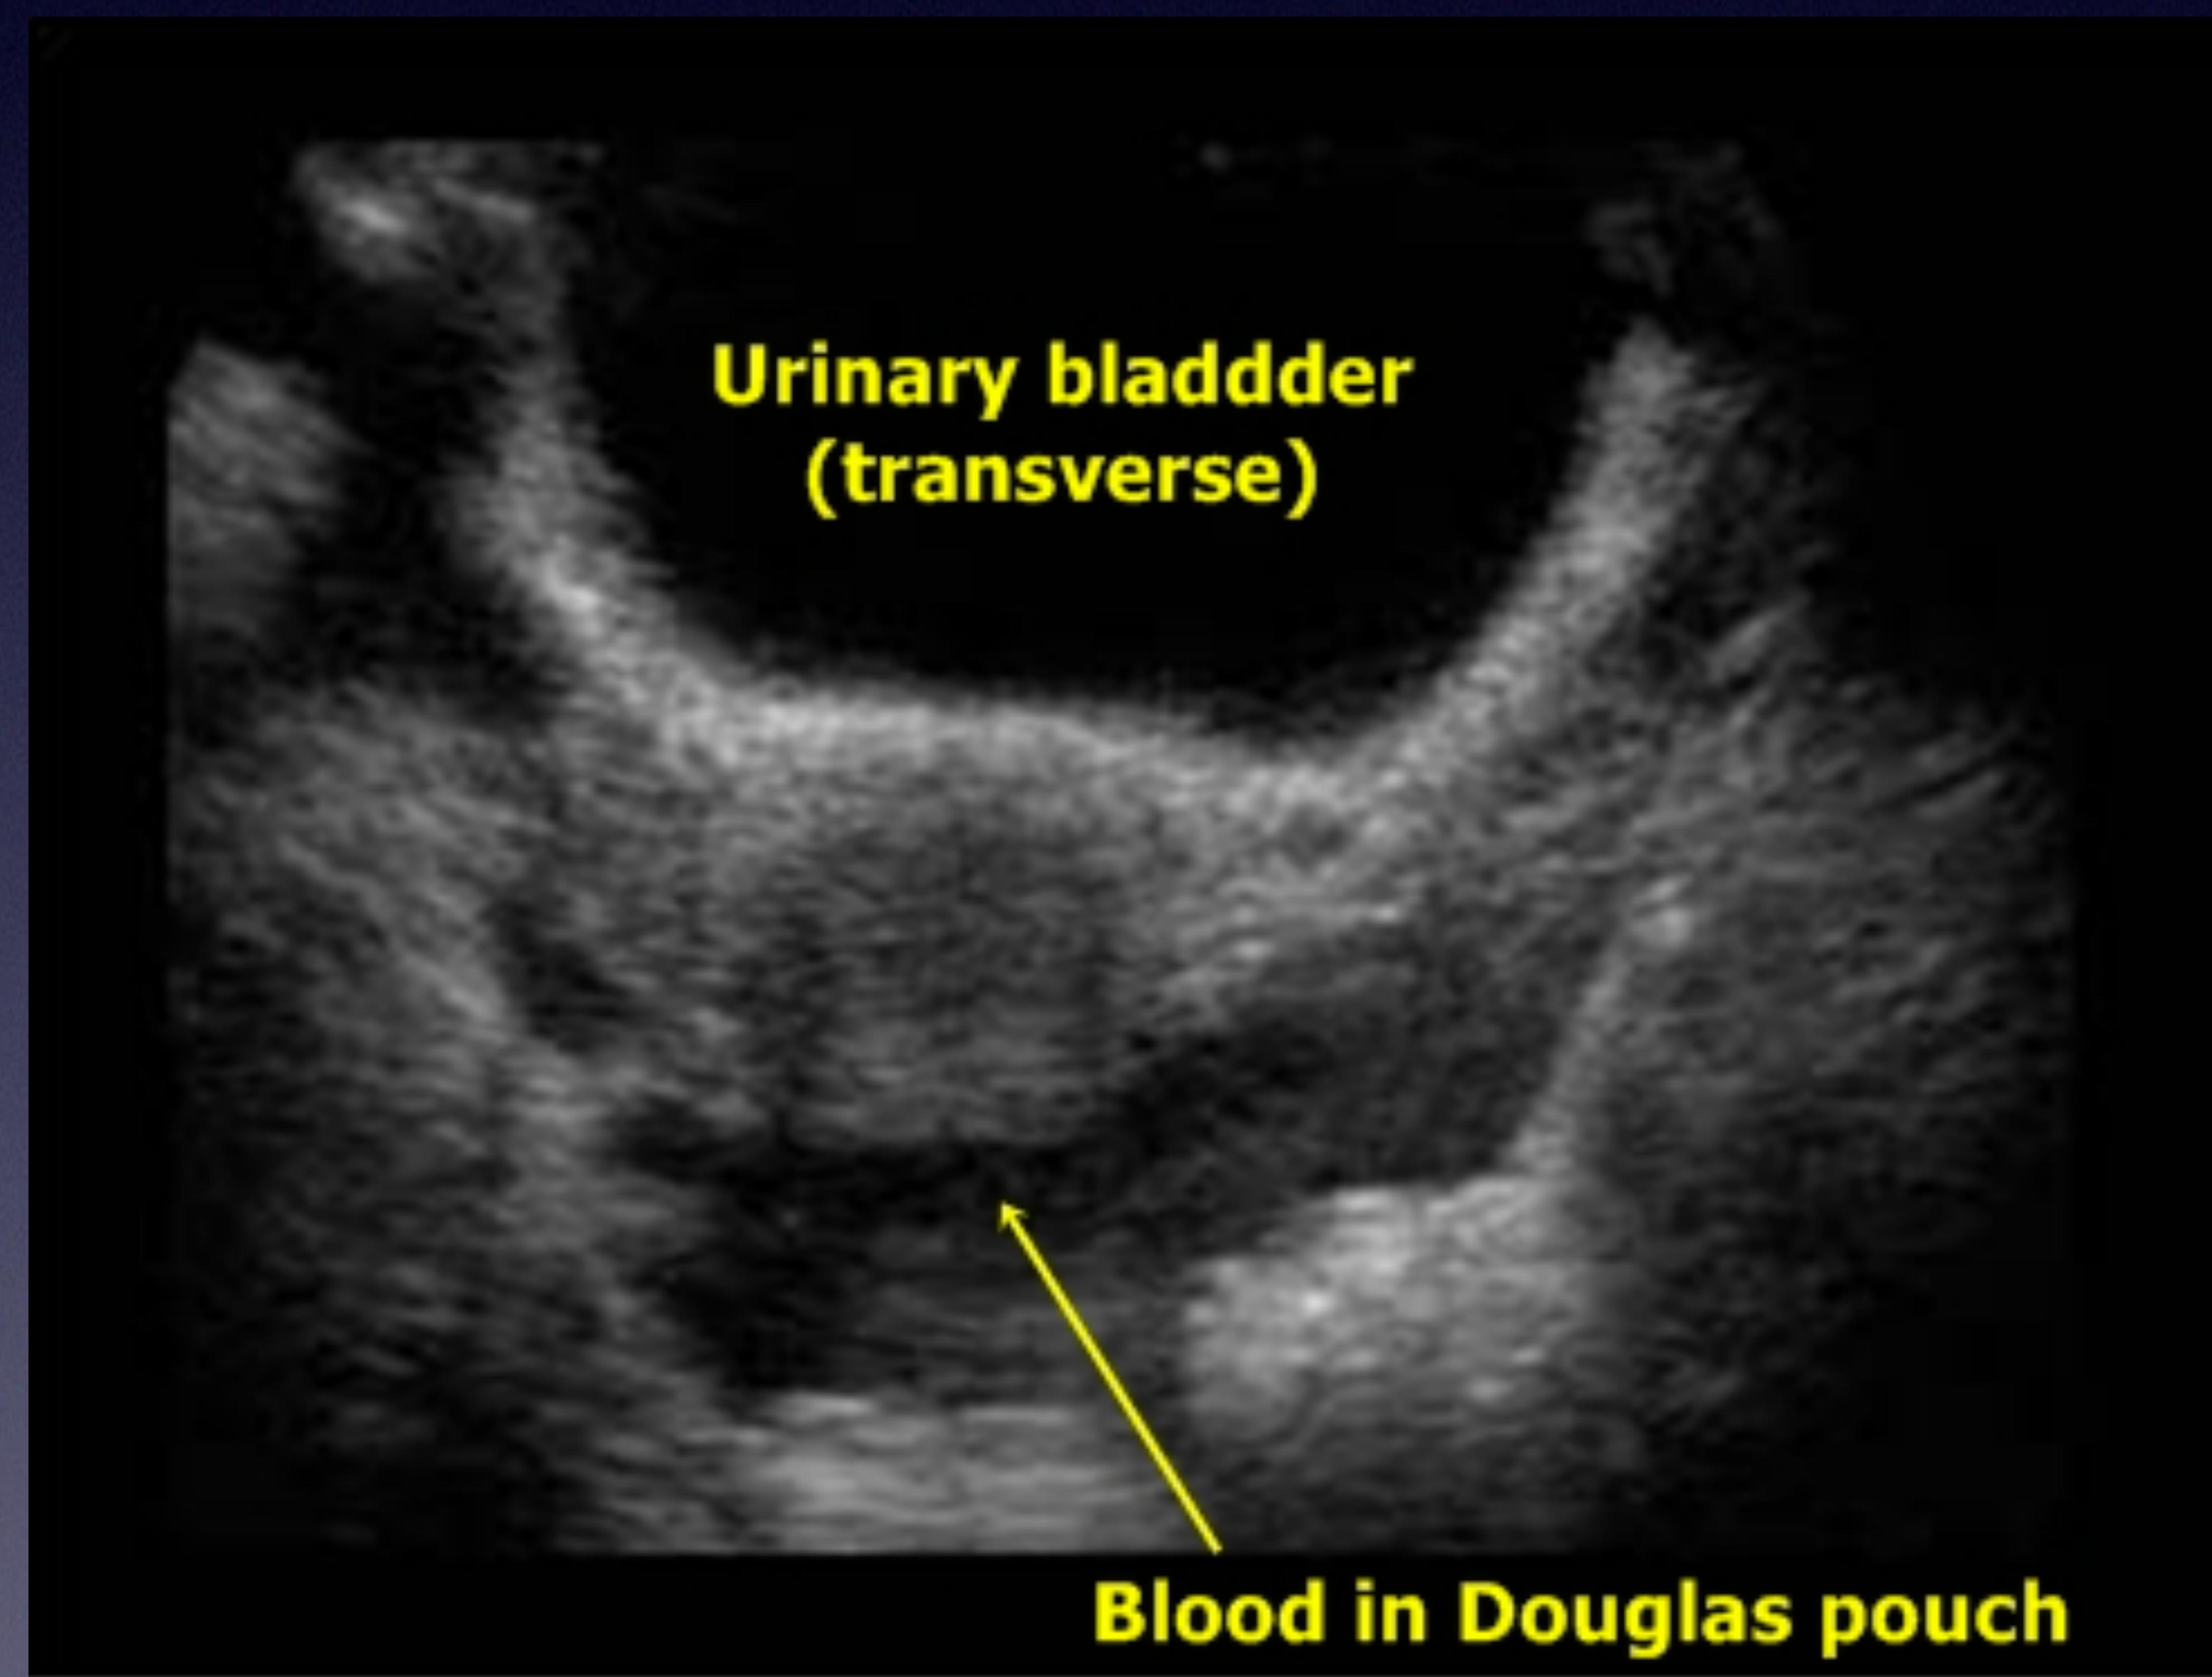

Bladder Scan (Suprapubic)

Midway between umbilicus and pubic bone.

Bladder full of urine (transverse view).

Blood in Douglas pouch (inferior to bladder).